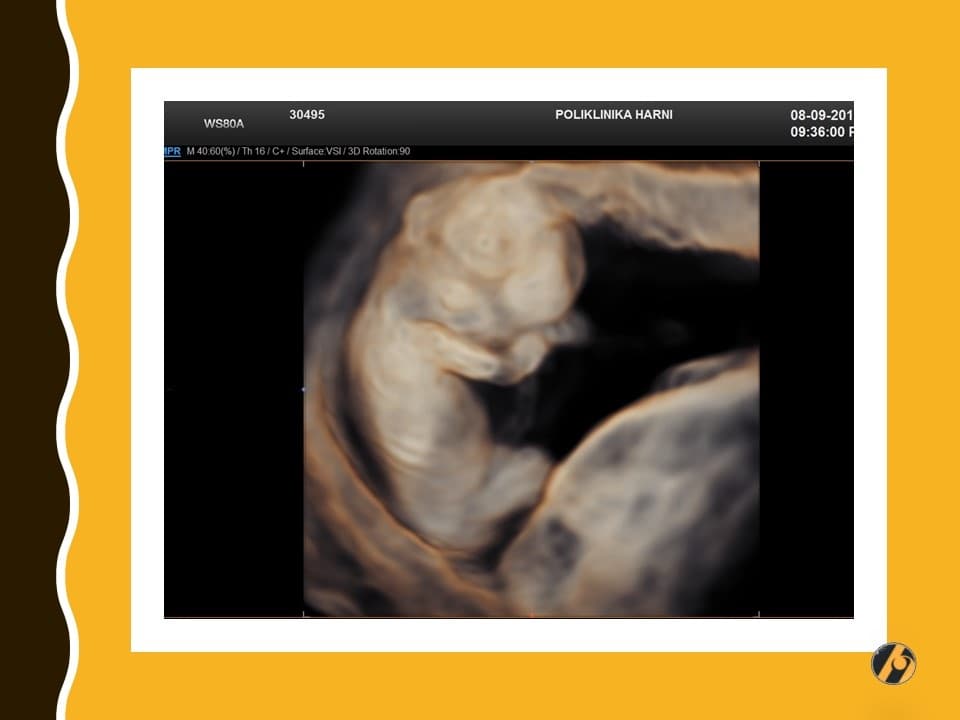

Lice vaše bebe sve je razvijenije. Prepoznaju se korijen nosa, formirani su obrazi, uši su sa strana na vratu prema glavi, a oči su sve bliže jedno drugome. Štitna žlijezda dovršila je svoj razvitak i spremna je za početak stvaranja vlastitih hormona.

Lanugo dlačice otpadaju, a vernix većim dijelom iščezava prije nego što će se beba roditi. Zajedno s lanugo dlačicama pokazuju se obrve, za sada veoma nejasno, čak niče i po koja vlas na glavi. Mišići lica se počinju kontrahirati, pa se nalicu mogu vidjeti grimase i zijevanje. Ispod zatvorenih očnih kapaka počinju se pokretati oči.

Vaša beba dugačka je 8.0 - 11.0 cm, a teška 30 - 60 g.